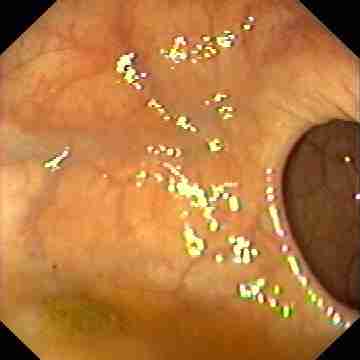

Appearance of normal colon.